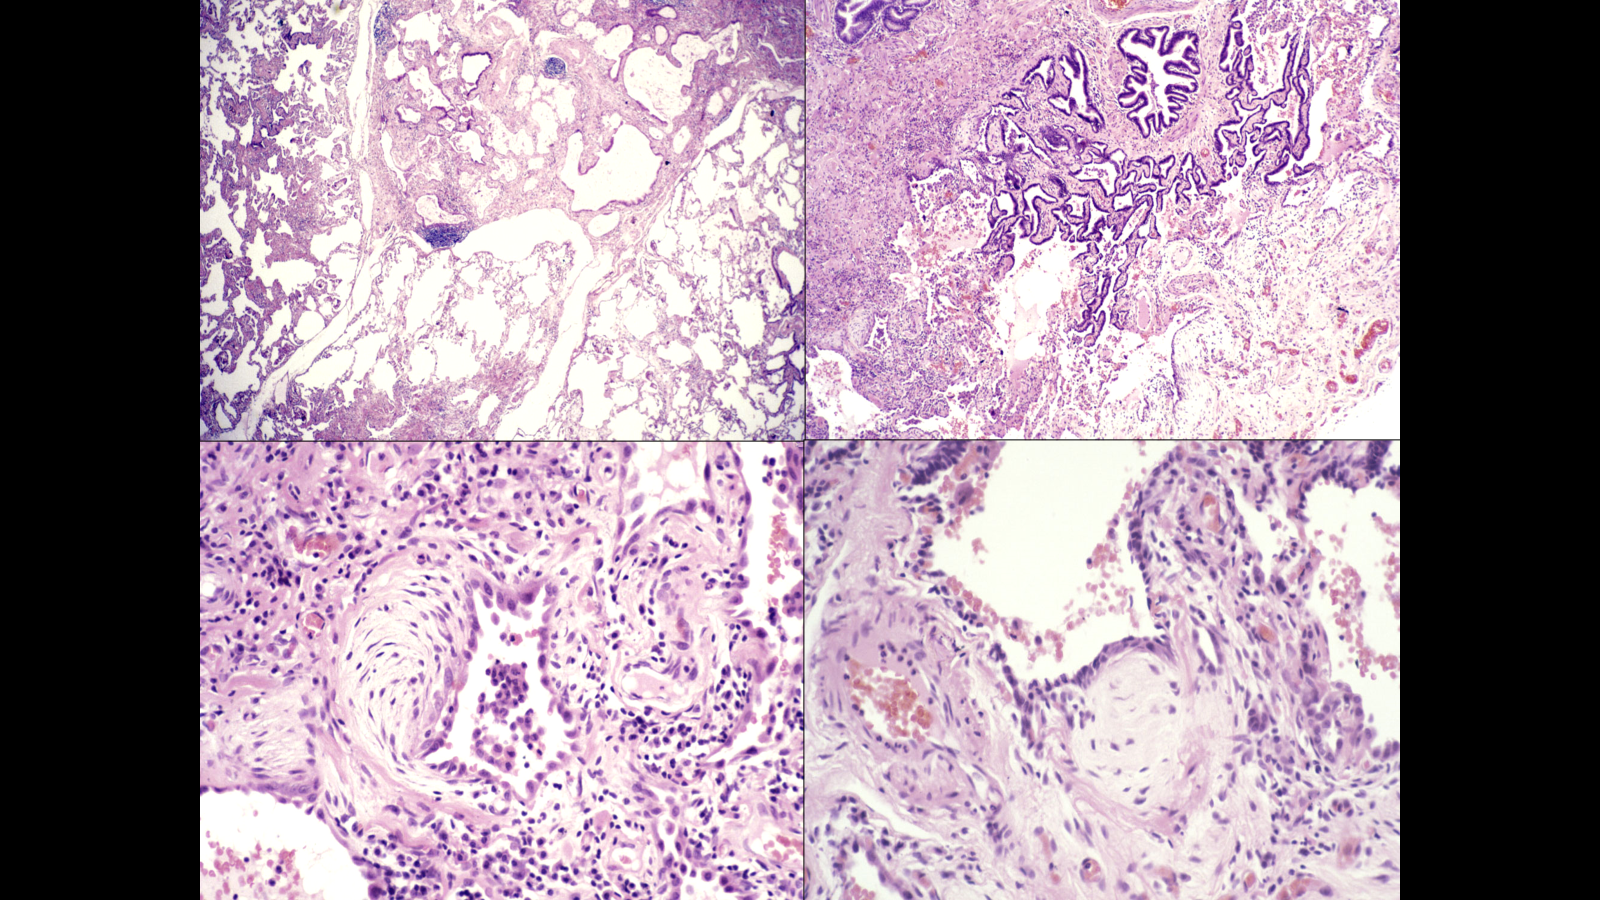

histopathology of UIP is patchy interstitial chronic inflammation

progressive accumulative damaging lung inflammatory process, goes over for a long period of time

eventually die of respiratory failure

in lower images fibroblastic fossi-key pathological change indicating damage and fibrosis that will scar up and lead to damaged lung